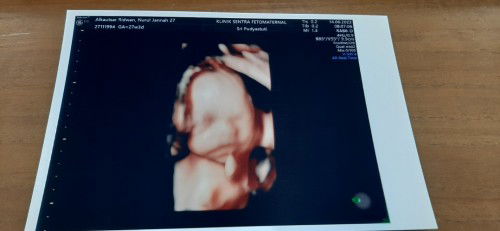

Dear Haha.. Halo sayangnya Mama Papa.. hari ini Haha tepat 39 minggu ada di perut Mama. Mama dan Papa sangat menanti kehadiran Haha sekarang. Mama dan Papa sudah mempersiapkan segala kebutuhan untuk Haha juga loh. Terima kasih sayang sudah hadir di perut Mama. Alhamdulillah Allah menghadirkan Haha untuk ada di perut Mama, untuk jadi buah hati Mama Papa, jadi malaikat kecil kami, yang di perut pun sudah sangat menggemaskan apa lagi nanti ketika Haha sudah lahir ke dunia. Pertama kali Mama tau kalo Mama hamil, Mama masih percaya ga percaya, yang lebih excited itu Papa loh. Alhamdulillah secepat itu Allah menghadirkan Haha di perut Mama. Mama dan Papa bener-bener ga kejar target buat cepet punya anak waktu itu, Mama Papa punya prinsip santai, kalau cepet dikasih Alhamdulillah, ga langsung dikasih juga gapapa. Alhamdulillah rezeki Mama Papa punya Haha dikasih cepet sama Allah, makanya Mama masih percaya ga percaya, dan baru percaya pas udah periksa ke dokter. Pas pertama kali Mama Papa denger detak jantung Haha juga Mama Papa terharu. Apalagi Mama. Masih ga nyangka ada makhluk kecil menggemaskan dalam perut Mama. Keajaiban untuk Mama perut Mama dari hari ke hari semakin membesar, makin percaya, di perut Mama ada Haha yang tiap harinya bertumbuh, berkembang dengan baik. Terima kasih ya sayang, solehnya Mama Papa, sudah bertumbuh dan berkembang dengan baik, semoga sempurna ya nak, ga ada kekurangan suatu apapun, aamiin.. Sayang.. tau ga pas pertama kali Mama ngerasain Haha bergerak di perut Mama, Mama bener-bener seneng, bener-bener excited, Mama beneran hamil, Mama beneran mau punya bayi lucu. Tiap harinya, Haha semakin aktif, sampe kadang buat Mama kaget. Tendangan Haha lumayan keras. Tapi gapapa sayang, itu tandanya Haha sehat ya nak, tanda sayang juga dari Haha untuk Mama, cara komunikasi Haha juga ke Mama Papa. Haha juga kalo ditanya Mama atau Papa, atau Nenek atau Babah, bahkan ditanya sama Enin, Haha selalu respon jawabannya dengan pergerakan Haha di perut Mama. Anak pinternya Mama Papa, udah ngerti ya sayang kalo diajak ngobrol, makanya Mama Papa seneng banget ngajakin Haha ngobrol. Qadarullah, terakhir kontrol Haha kemarin, dokter menyarankan agar Haha lahir secara caesar. Mama dan Papa sama sekali ga keberatan Haha harus lahir secara caesar, yang penting keselamatan Haha dan Mama. Mama dan Papa semakin ga sabar buat cepet ketemu Haha, buat cepet gendong Haha. Sayang, maafin Mama ya kalo nanti Mama banyak salah ke Haha, ini pertama kalinya Mama jadi seorang Mama. Mama tiap hari bakal belajar terus buat jadi Mama yang baik buat Haha, buat jagain Haha, ngedidik Haha juga. Mudah-mudahan Mama ga cuman jadi Mama buat Haha, bisa jadi temen atau sahabatnya Haha juga ya sayang. Sekali lagi, terima kasih sayang sudah membersamai Mama, sudah jadi anak Mama Papa. Semoga Haha bisa sehat terus, panjang umur, jadi anak yang soleh, pinter, bijaksana, dan jujur ya nak. Aamiin.. Sampai ketemu sayang. Mama dan Papa akan selalu sayang Haha. We love you Haha ❤ With love, Mama